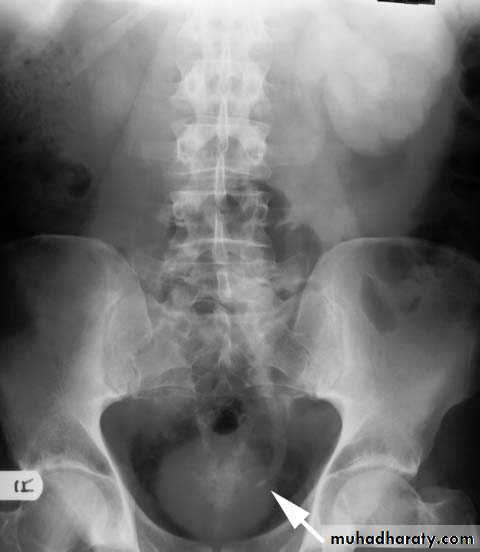

Infestation With Schistosoma haematobium. Plain radiograph demonstrates calcification in the wall of the bladder (open arrows) and in the wall of the left ureter (curved arrow). The bladder is filled with urine